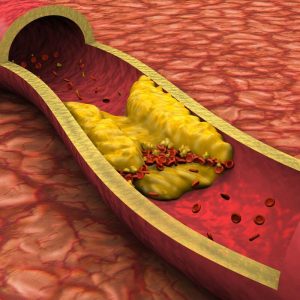

Cholesterolio kiekio mažinimas

Didelis cholesterolio kiekis padvigubina širdies ligų riziką. Vienas tyrimas atskleidė, kad žmonėms, kurie tris kartus per dieną vartojo 8 gramus aktyvintos anglies, jų MTL blogojo cholesterolio lygis sumažėjo 41%, o gerojo DTL cholesterolio kiekis padidėjo 8%!

Šis poveikis ypač svarbus žmonėms, turintiems širdies ir kraujagyslių riziką. Aktyvuota anglis padeda išlaikyti sveiką kraujotaką ir reguliuoti lipidų balansą, todėl sumažėja aterosklerozės ir širdies priepuolių tikimybė.